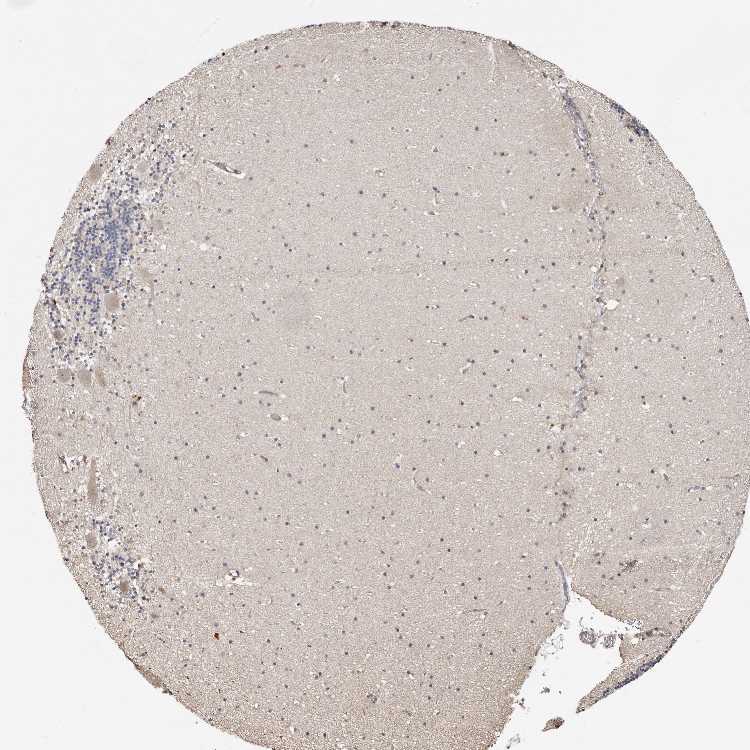

CEREBELLUM - Antibody stainingi

Antibody staining in the annotated cell types in the current human tissue is reported as not detected, low, medium, or high, based on conventional immunohistochemistry profiling in selected tissues. This score is based on the combination of the staining intensity and fraction of stained cells.

Each image is clickable and will lead to virtual microscopy that enables deeper exploration of all samples and also displays staining intensity scores, fraction scores and subcellular localization as well as patient and tissue information for each sample.

Antibody HPA028604Antibody HPA028689

Purkinje cells LowHigh

Cells in granular layer Not detectedLow

Cells in molecular layer Not detectedLow